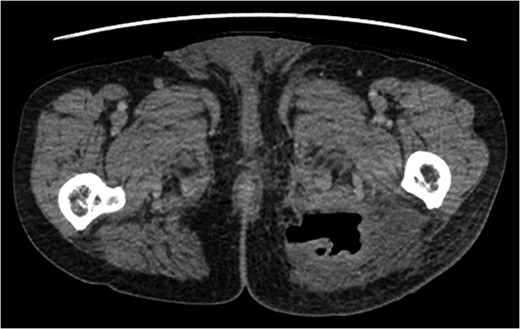

A rare complication of diverticular disease is the formation of fistulas, most commonly either colo-vesical or colo-vaginal. We present the unusual case of a perforated sigmoid diverticulum forming a colo-gluteal fistula and presenting initially as a gluteal abscess in an otherwise asymptomatic patient. After drainage of the gluteal abscess, the patient re-presented with faecal loss from the abscess drainage site. Imaging revealed fistulous communication between the sigmoid and the left obturator internus muscle, tracking to the gluteus maximus with associated abscess and cutaneous communication to the site of previous drainage. The patient underwent an emergency Hartmann's procedure with lay open/abscess drainage of the gluteal cavity. Post-operatively the patient experienced continuing discharge from the gluteal fistula despite repeated drainage and debridement causing considerable morbidity, inconvenience and misery. Clinicians should maintain a high index of suspicion when presented with a gluteal abscess and should consider the possibility of an intra-abdominal source.

The patient re-presented a week after discharge, complaining off persistent pain around the buttock, with feculent discharge and flatulence from the wound. Abscess cultures from the previous admission were reviewed and noted to have grown Escherichia coli and clostridium species.

An emergency Hartmann's procedure was performed under general anaesthetic through a lower midline incision as well as lay open of the perineal fistula. On opening the abdomen, a perforated diverticulum was identified extending into the left lateral pelvic wall. A standard Hartmann's procedure was performed, with sigmoid colectomy, division of rectum at recto-sigmoid junction and a tension-free stoma formed in left hypochondrium. The left buttock abscess cavity extended by a further 2–3 in. and the cavity then packed.